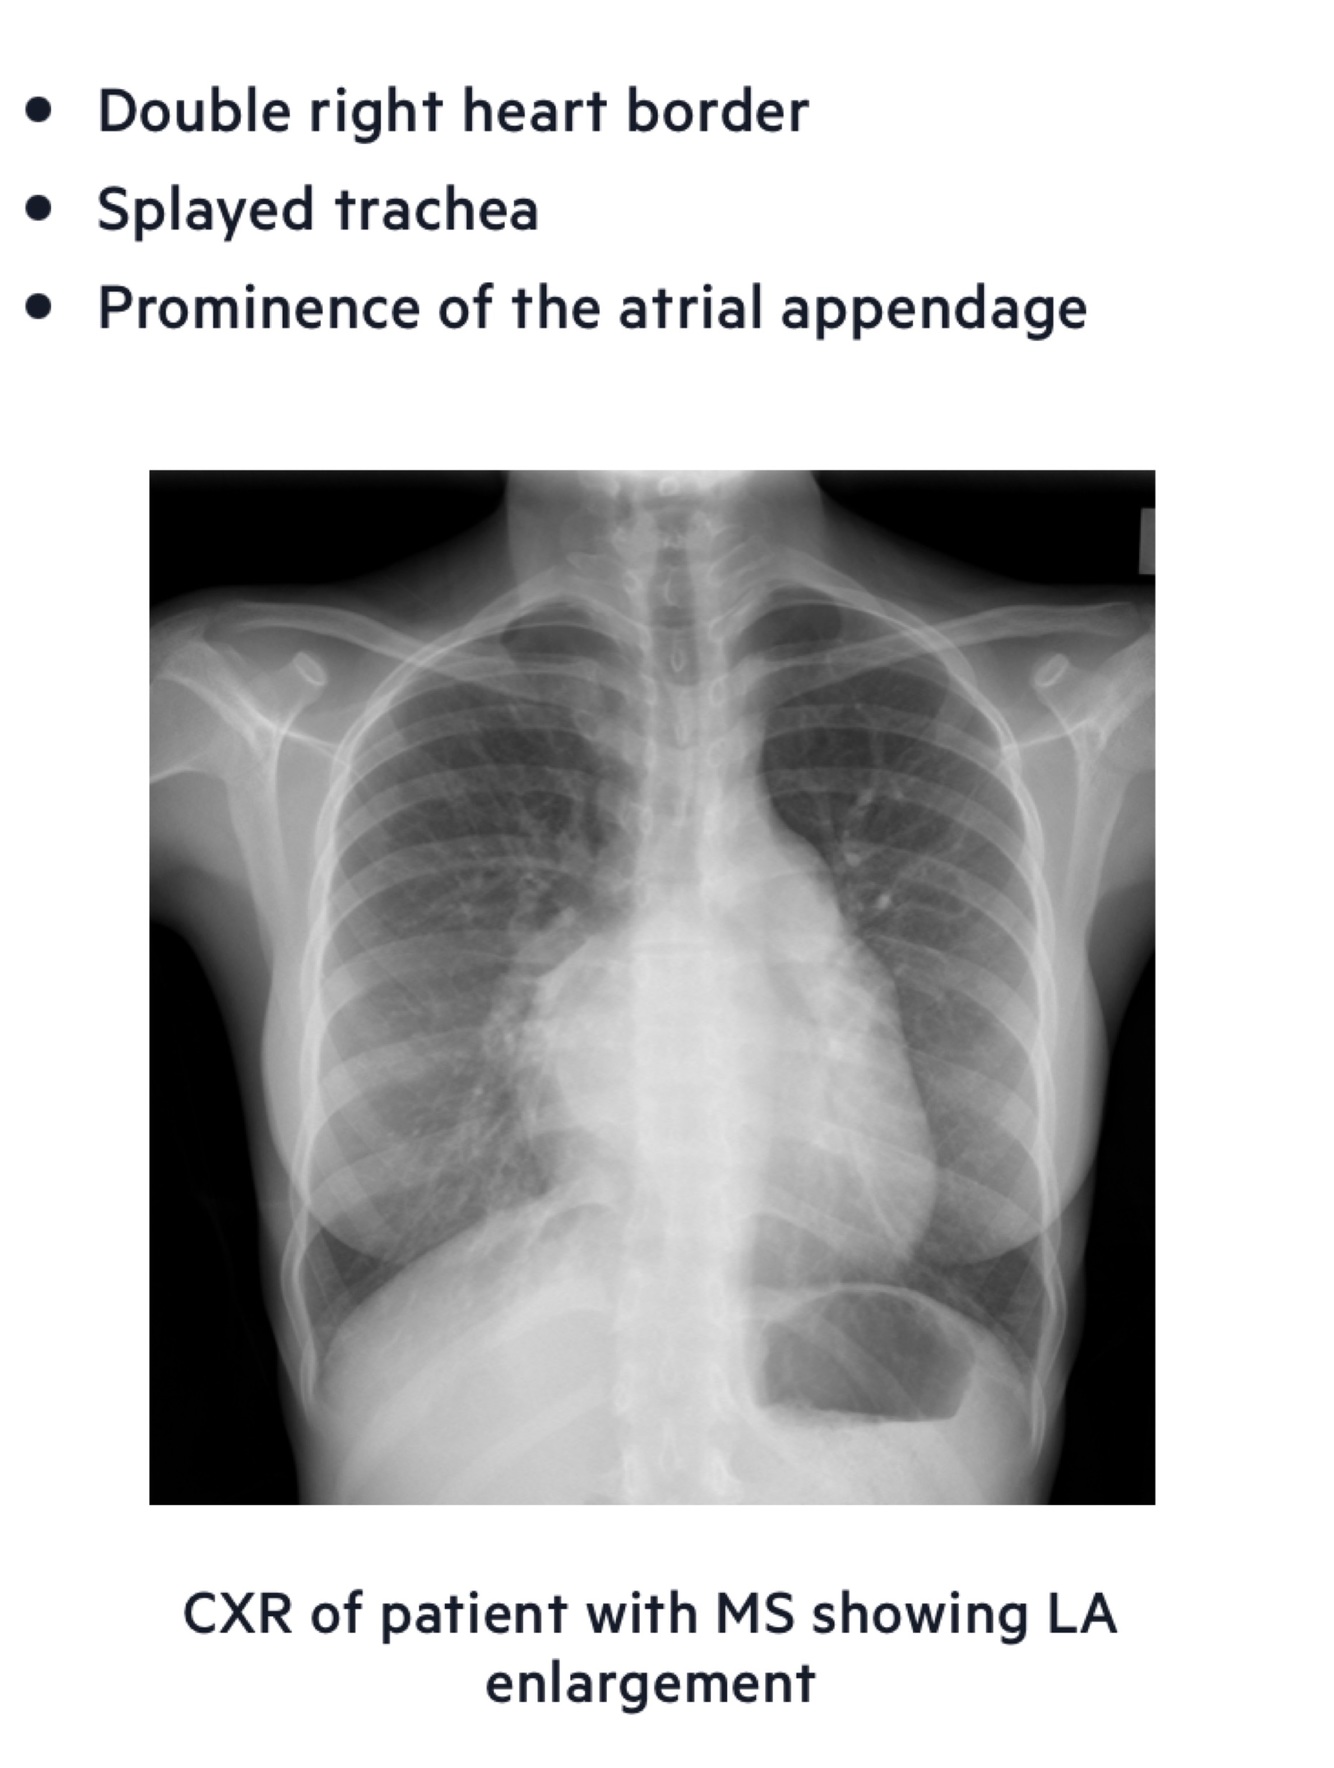

On the CXR left atrial enlargement can be seen. In those with pulmonary hypertension signs of this and right sided heart failure may also feature. The CXR shown below has a number of signs indicative of left atrial enlargement - what murmur is this describing?

On the CXR left atrial enlargement can be seen. In those with pulmonary hypertension signs of this and right sided heart failure may also feature. The CXR shown below has a number of signs indicative of left atrial enlargement: